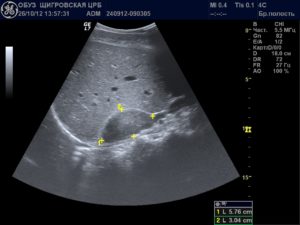

В норме каждая почка у взрослого человека должна соответствовать размерам:

- длина 10-12 см;

- ширина 5-6 см;

- толщина 4-5 см;

- толщина паренхимы колеблется в пределах 15-25 мм.

Допускается отклонение в размерах на 2 см по каждому из показателей. По форме здоровая почка напоминает фасолину. Положение забрюшинное, находятся с обеих сторон от позвоночника напротив 12 грудного, 1 и 2 поясничных позвонков, при чем, правая почка лежит немного ниже левой. Во время дыхания может быть смещение на 2-3 см. Жировая клетчатка со всех сторон обволакивает почку.

Структура почечной ткани должна быть однородной или гомогенной, без каких-либо включений. Корково-медуллярная дифференциация или видимость почечных пирамидок выражена отчетливо. Почечная лоханка, представляет собой полость внутри почки – без содержания включений.

Для взрослых размерами почек в норме считается:

- длина – 100-120 мм;

- ширина – 50-60 мм;

- толщина – 40-50 мм.